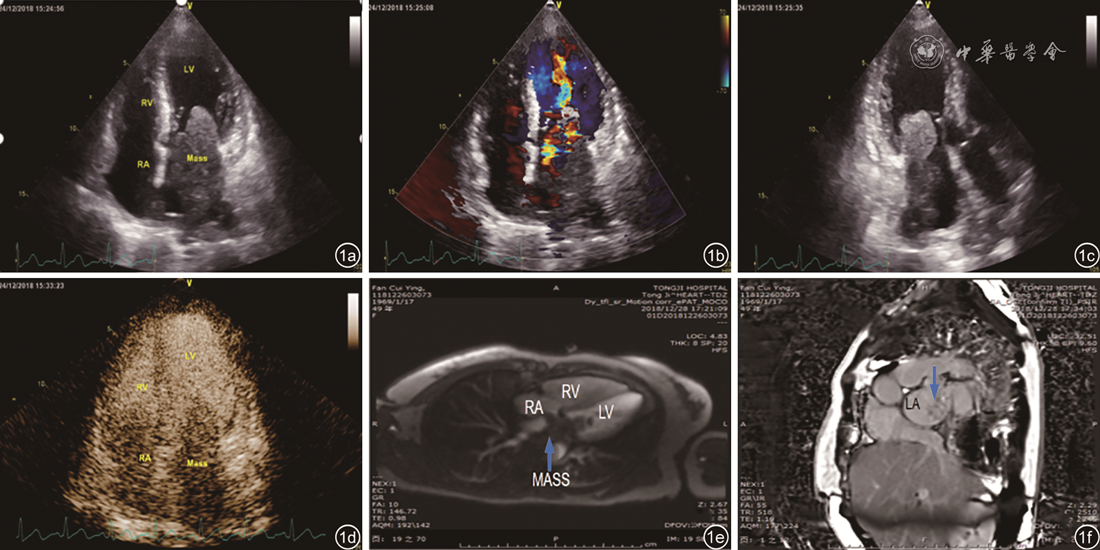

图1 左心房梭形细胞肉瘤超声及磁共振图像。图a~c为常规经胸超声心动图显示左心房后壁较大实质性肿块,并导致二尖瓣口狭窄;图d为心脏超声造影显示左心房肿块内丰富造影剂充填,提示该肿块富含血供;图e、f为心脏磁共振检查显示肿块首过灌注轻度强化,延迟增强不均匀强化(箭头所示为肿块)注:LA为左心房;LV为左心室;RA为右心房;RV为右心室;MASS为肿块